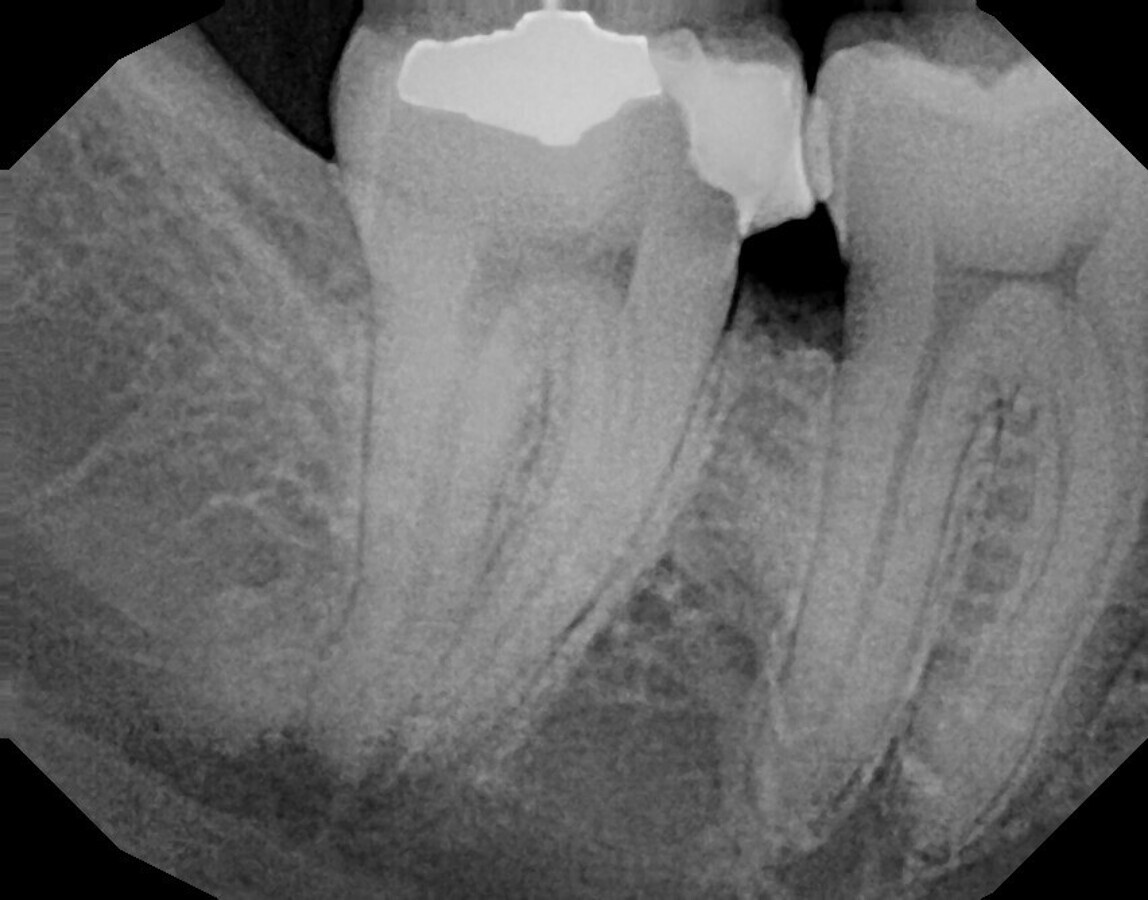

Fig. 4: Course of the root canal in the post-op radiograph.

However, the most amazing thing of all is that, in Jeni mode, the endodontic motor even knows when it is time to irrigate. After the acoustic signal, the current file was removed from the canal and rinsed with sodium hypochlorite and then with chlorhexidine at appropriate intervals. Obturation was performed as usual with gutta-percha points in combination with bioceramic sealer. The final radiograph shows the root canal system following the natural anatomy. It had been thoroughly prepared and reliably sealed with gutta-percha (Fig. 4). The satisfied patient was discharged. The long-term results hopefully will be seen in the follow-up.